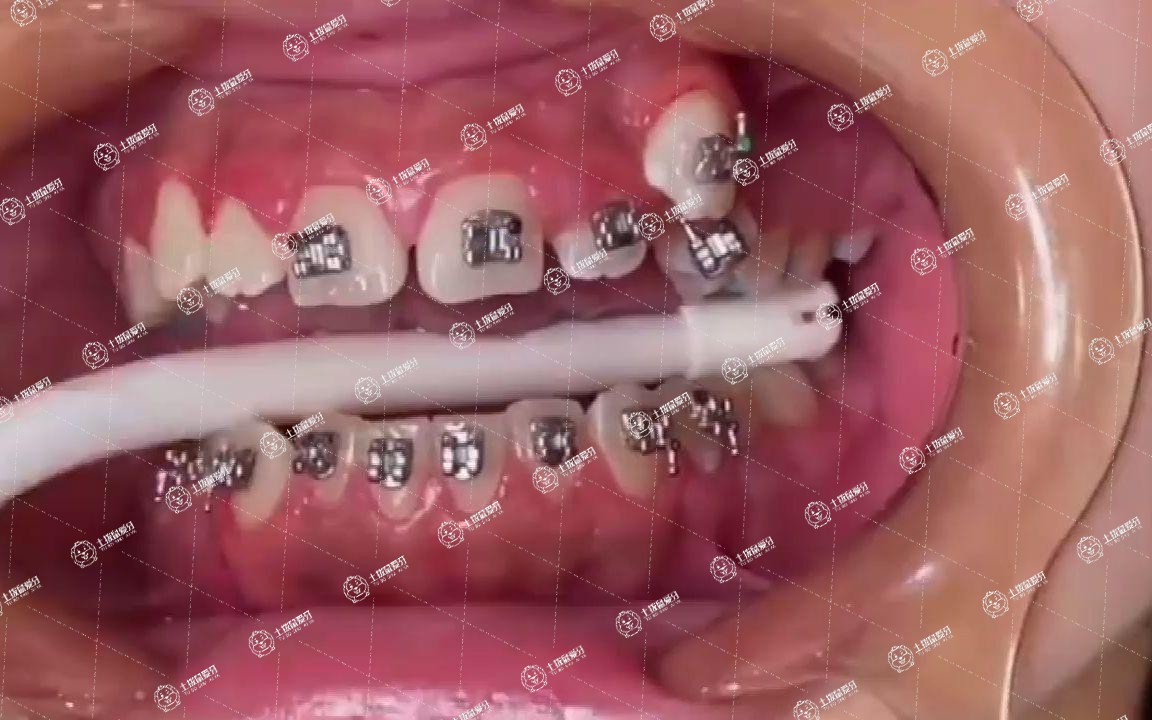

牙釉質(zhì)脫礦及齲病。正畸過程中,由于口腔內(nèi)多了許多矯治裝置,因此如果還依照平日的清潔習(xí)慣,就會(huì)遺漏許多不易清潔的地方,容易造成牙齒表面不可逆脫礦,嚴(yán)重的還可能發(fā)生齲病。

30歲牙齒矯正者,需到專業(yè)口腔醫(yī)療機(jī)構(gòu)就診,完善檢查,在專業(yè)醫(yī)師指導(dǎo)下規(guī)范治療。

1.牙齒矯正并沒有嚴(yán)格的年齡限制,一般30歲左右也可以進(jìn)行牙齒矯正,戴牙套也能夠矯正牙齒畸形,讓牙齒更加整齊,但是在進(jìn)行牙齒矯正時(shí)一定要選擇正規(guī)的醫(yī)院,這樣才能夠達(dá)到比較好的效果。

進(jìn)行牙齒矯正并沒有嚴(yán)格的年齡限制,因此不必有過大的心理壓力,牙齒矯正后需要注意個(gè)人衛(wèi)生,定期復(fù)查。